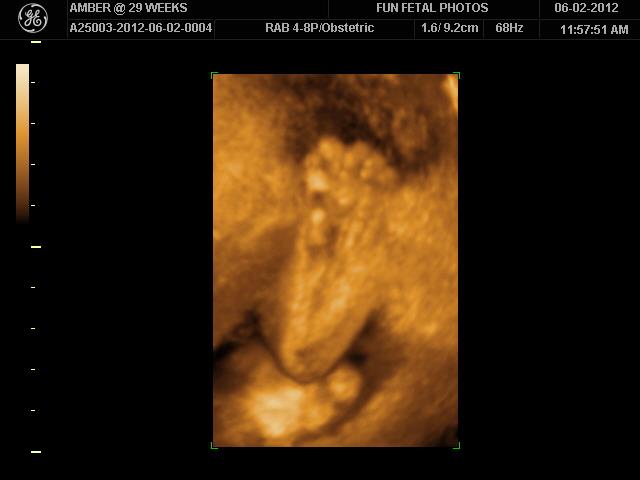

We had our 3D ultrasound on Saturday and WOW! Getting to see him in 3D was pretty darn cool and this might sound strange, but made him seem so much more real. The level of detail was amazing and it was fun watching him move around in there.  So stinking cute. Here are a few pics.